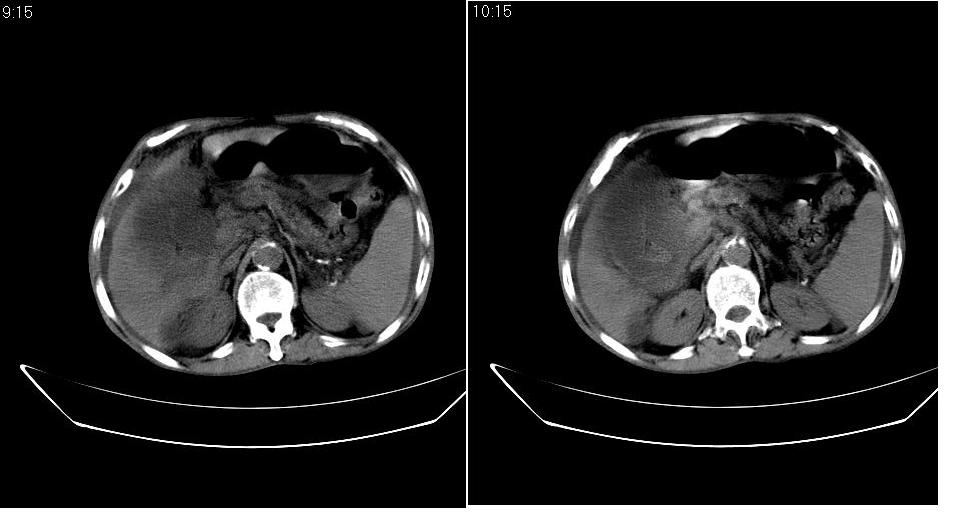

男 78岁,全身黄染,病人家属拒绝增强。

胆总管下端梗阻(原因待查)伴肝内外胆管扩张、胆囊积水。

肝周 脾周 胆囊窝内明显积液,胆囊扩大,胆囊壁模糊,肝内胆管扩张。考虑;胆囊癌周边侵润伴腹水。

1、梗阻性黄疸(胆总管下段病变或十二指肠病变)。

2、胆囊炎,腹水。